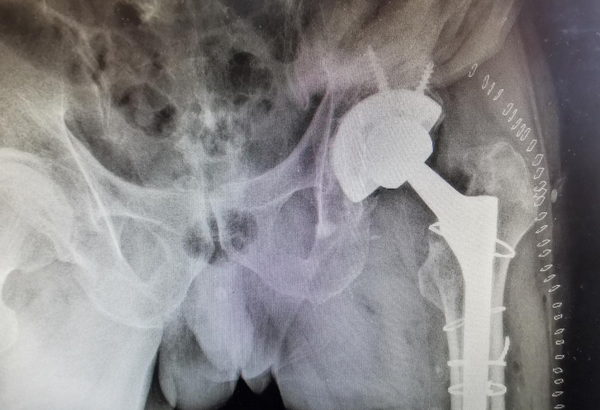

患者术后X线

近日,家住齐齐哈尔市的张大爷因左侧髋关节疼痛难忍,慕名来到齐医附属二院骨外科四病区(运动医学科)就诊,李宝权主任通过询问张大爷病史得知,该患者13年前因外伤导致左侧股骨颈骨折,行全髋关节置换手术治疗,近期感到左髋关节疼痛明显伴有习惯性脱位,导致不能行走,严重影响日常生活。李宝权主任带领团队认真研究患者病情,对患者进行了仔细查体,结合影像检查,经过充分考虑并与患者沟通后,决定为其行全髋关节假体翻修术。在李宝权主任团队及麻醉师、手术室的共同配合下,经过三个多小时紧张的手术,张大爷安全平稳的返回病房。术后患者恢复良好,左侧髋关节疼痛症状完全缓解,张大爷激动的表示自己的腿不疼了,衷心感谢齐医附属二院骨外科四病区李宝权主任团队的付出。

全髋关节假体翻修术原因包括假体松动、假体周围骨折、假体周围感染等,所有翻修手术因大多都存在不同程度骨缺损,如何重建骨缺损通常是比较困难的挑战。

髋关节翻修术是关节外科医师所面临的挑战,术中稍有处理不当就会导致假体早期松动致翻修术失败。人工髋关节置换术后翻修对于关节外科医师仍然是极具挑战的难题,其不仅在于手术的难度,更在于对初次手术失败原因的判断、骨缺损的评估、手术方式和假体的选择等问题。

其手术操作的关键是假体取出及翻修假体的顺利安放:术前需要充分准备多种类型的髋臼假体,并根据患者身体情况和术中髋关节的具体情况进行选择;术中需要对骨缺损进行充分的植骨。